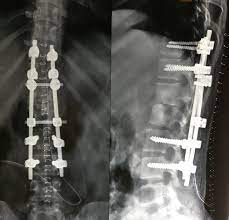

Spine Fixation Treatment In Nashik

Spinal fixation devices provide stability and restore anatomic alignment in the treatment of fractures, degenerative disease, infection, and tumors and correct congenital deformities such as those seen in scoliosis

Spine Fixation